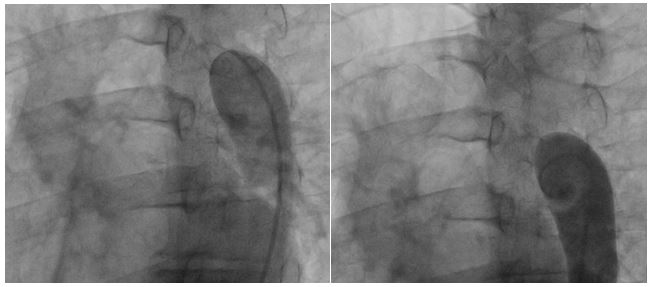

There were no perioperative complications with minimal postoperative bleeding. Extubation occurred 24 hours after surgery. The patient was transferred from the intensive care unit to the intermediate care unit on postoperative day two, and he was finally discharged from the hospital at postoperative day six. Control chest CT angiography revealed a patent graft and good distal flow (Fig. 8 and Fig. 9). The patient recovered uneventfully and continues doing well.

Figure 8: Postoperative chest CT angiogram 3D reconstruction.